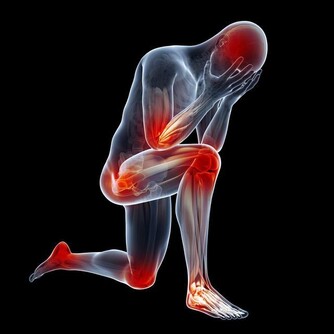

人體除了特定器官外,全部都受脊髓神經所支配,如果各個支配器官神經與脊髓之間傳導暢通無阻,各個器官就可發揮正常,一旦脊髓神經系統受壓迫便容易病變,每一椎別供應人體各個部位。